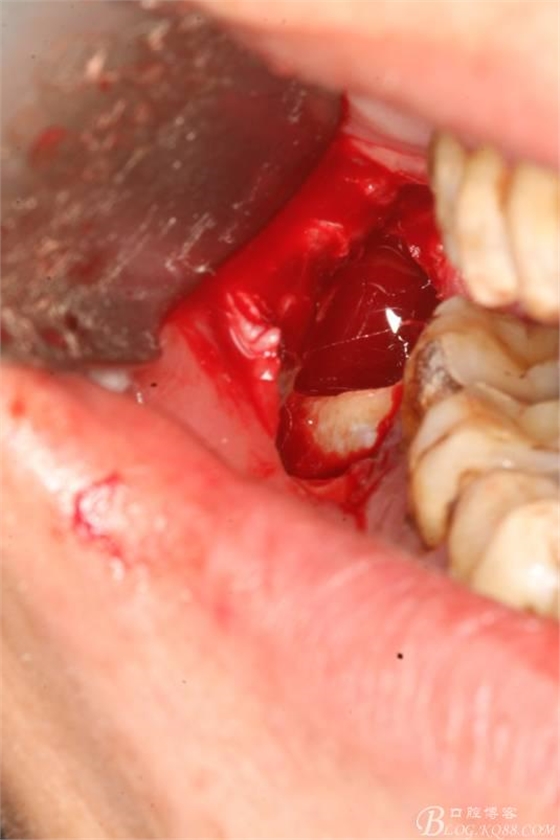

3.去骨、暴露48.

4.縱分牙根和牙冠